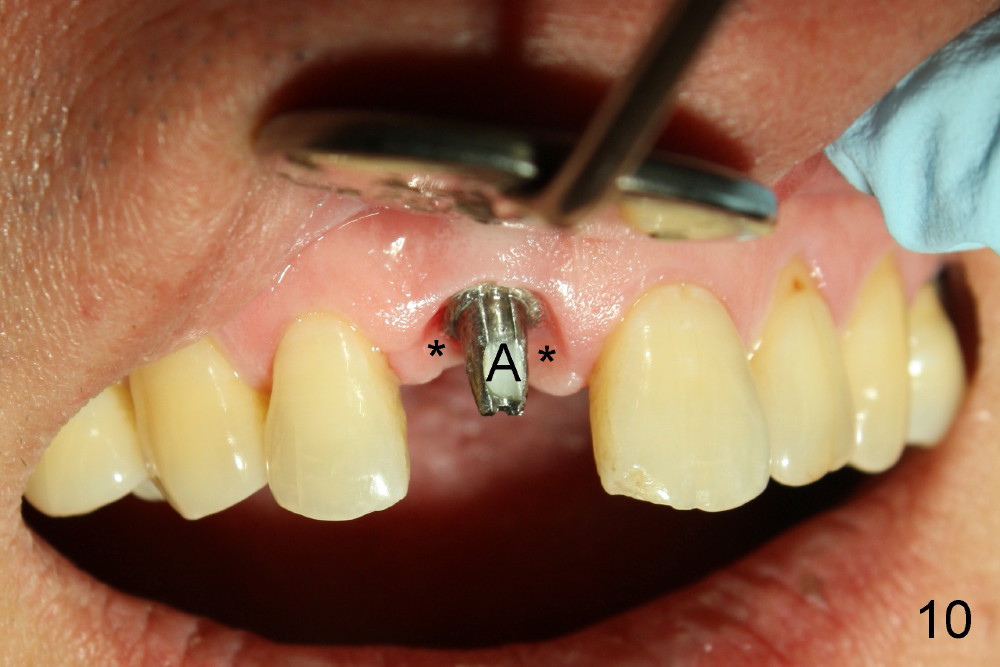

The provisional is dislodged 3.5 months postop; there is no labial atrophy (Fig.8 black arrowhead). The permanent crown (Fig.9 C) is harmonious with the papillae (*). When the try in crown is removed, the gingival tissue looks healthy (Fig.10 *).